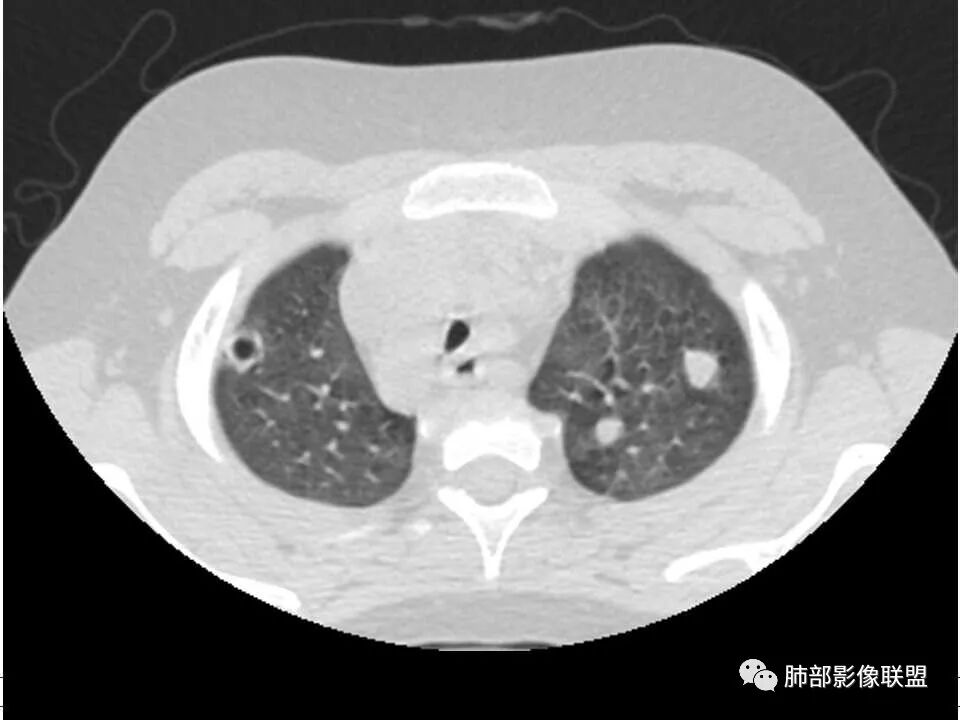

薄壁囊腔,结节,结合病史考虑LCH

考虑脓毒栓子,其次lch

男,8岁,两肺多发随机分布结节空洞影,壁光整,考虑血道来源,结合右侧膝关节有骨髓水肿信号,临床感染指标明显增高,考虑骨髓炎并血道播散,金葡菌感染?LCH小孩骨头症状相对较轻,放在代排吧。

小儿,急性起病,下肢疼痛,mr提示骨髓水肿,临床化验炎性指标高,考虑金葡菌骨髓炎,双肺多发结节,以血管支气管束及胸膜下分布为主,部分结节近端与血管相连,部分结节可见空腔,内壁光整,部分囊腔有张力,考虑骨髓炎并肺内血播感染,金葡?

2.双肺多发片影,随机分布,多空洞或囊腔,胸膜下多楔形影,气道未见受累等等符合脓毒血症影像学表现,尤其是金葡。

2、脓肿:实变区内脓肿,最常见吸入性金葡菌引起的多,下叶多见,在实变区中央,外壁不清,内壁光滑,可见气液平面;血源性脓肿,多发,结节状,大小无差异,边清,光滑,壁薄;

金葡菌的脓肿很少融合成团。

金葡菌囊和脓肿常互相转换。

气囊不是一开始就出来的,是慢慢,从厚到薄,最后吸收。这例就符合它的典型发展过程

就是说,第一次的CT ,只能考虑感染,建议复查,第二次的多发气囊出现,就要想到金葡菌的可能。继续复查变化一般非常快。